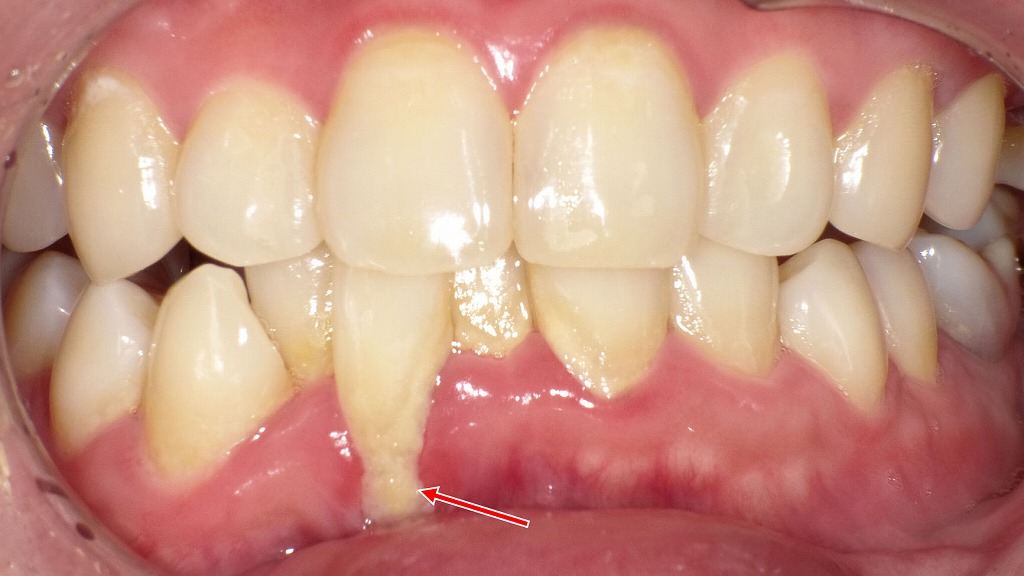

歯ぐきが下がって歯根が露出する歯肉裂開の部位に、歯石や歯垢が大量に付着しています。これらは歯周病菌の温床となり、硫黄化合物などの強い悪臭ガスを発生させるため、「うんちのような口臭」の原因になります。見た目では分かりにくくても、歯周病が進行しているサインの一つであり、早めの歯科でのクリーニングと歯周病治療が重要です。